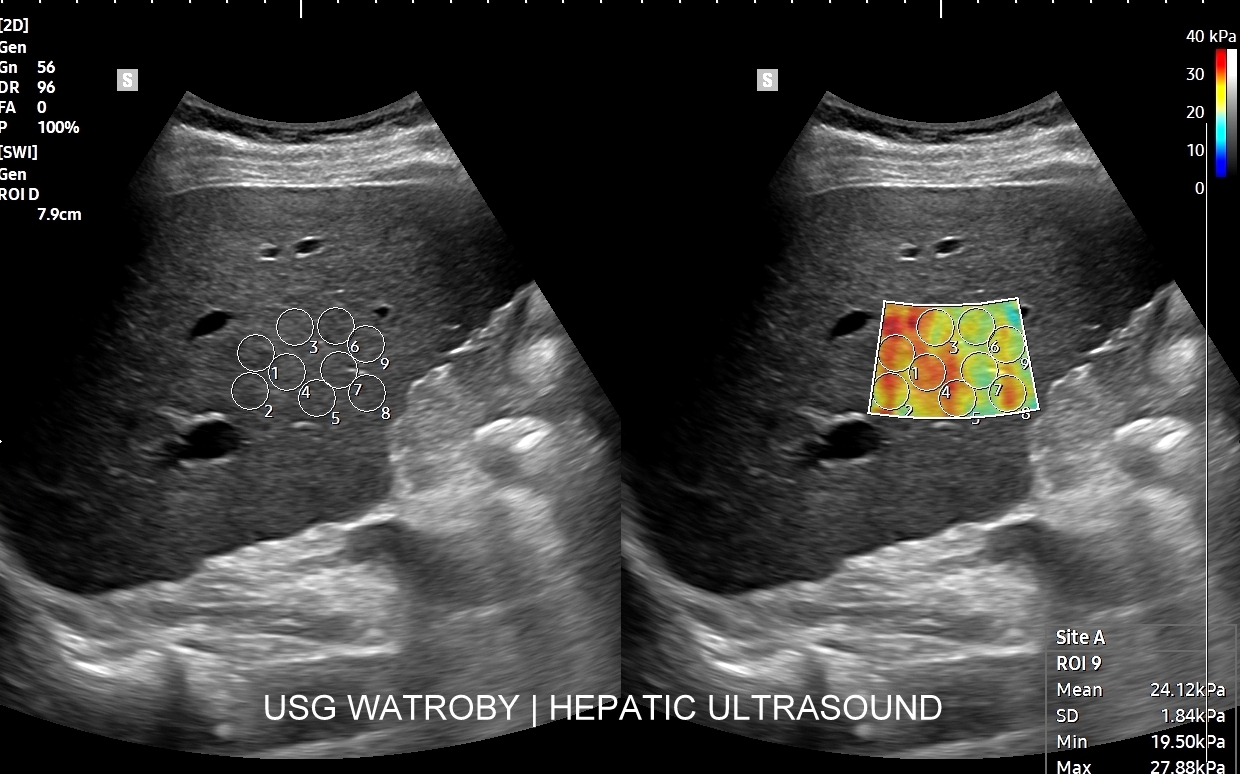

Badanie multiparametryczne MPUS jamy brzusznej

Rozwinięciem standardowego badania USG jamy brzusznej jest badanie multiparametryczne MPUS (ang. multiparametric ultrasound), w ramach którego wykorzystuje się różnorodne, nowoczesne modalności sonograficzne, takie jak tryby mikrounaczynienia MVI, B-flow, elastografię, ilościową ocenę stłuszczenia wątroby QUS, czy tryb Dopplera spektralnego, a to wszystko w celu uzyskania dodatkowej oceny funkcjonalnej i biologicznej struktur, narządów oraz tkanek jamy brzusznej. Obrazowanie MPUS niejednokrotnie poprawia także wizualną ocenę narządów wewnętrznych, czego przykładem jest zastosowanie trybu MVI w ramach bezkontrastowej angiografii sonograficznej naczyń oraz w ocenie guzów nerek. Klasycznymi i najczęstszymi zastosowaniami badania MPUS są jednakże funkcjonalna ocena wątroby w kierunku stłuszczenia, zwłóknienia, zapalenia i nadciśnienia wrotnego, a także ocena żywotności i funkcji nerek.

• Możliwość rozszerzenia zakresu badania USG w razie wystąpienia konieczności. Praktycznymi przykładami są zastosowanie trybu MVI w przypadku wykrycia guzka w nerce, czy przeprowadzenie badania elastograficznego i dopplerowskiego w wypadku stwierdzenia nieprawidłowego obrazu wątroby.